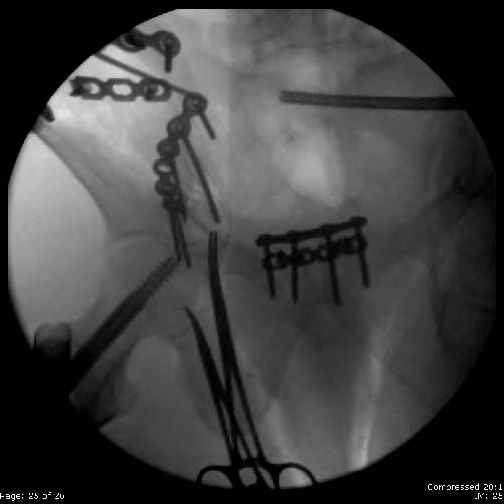

Here are the postop fluoros.

Then 6-hole plate along brim with 1 screw in R sacral ala. Then lagged 2 screws along crest A --> P. finally 10-hole plate along inner aspect of crest. R posterior ilium still a bit stepped off.

Fluoroed L SI joint and it seemed stable, but wide. So, applied c-clamp to try to squeeze down L SI joint (and note, on the last slide attached, that it's still wide), and got it closer. Single perc Iliosacral screw 40mm thread.

Applied second plate anteriorly on symphysis as I wasn't confident L SI was as stable as it could be and wanted to protect it better.